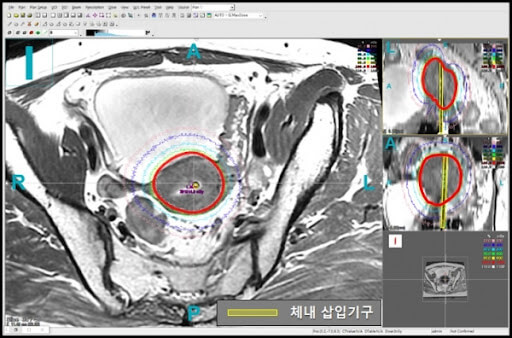

근접치료는 방사선 치료의 한 형태로, 밀봉된 방사선원(동위원소)을 환자의 치료 부위에 직접 삽입하거나 근접시켜 방사선을 조사하는 방법입니다. 이 치료법은 주로 종양 치료에 사용되며, Brachytherapy라고도 불립니다. 근접치료는 종양에 대한 집중적인 치료를 제공하면서도 주변의 건강한 조직을 보호하는 데 중점을 둡니다. 아래에서는 근접치료의 개념, 원리, 장단점 등에 대해 자세히 알아보겠습니다.

근접치료는 종양 치료의 한 형태로, 종양이나 병변에 인접한 조직이나 중요한 구조에 직접적으로 방사선을 적용하여 치료하는 방법입니다. 이는 종양 주변 조직이나 장기에 방사선을 집중적으로 전달함으로써 종양의 성장을 억제하거나 제거하는 것을 목표로 합니다. 주변 조직의 손상을 최소화하는 것이 근접치료의 핵심 중 하나입니다.

근접치료는 종양이나 병변에 인접한 조직이나 중요한 구조에 방사선을 직접 적용하여 치료하는 방법입니다. 이 방법은 종양 주변 조직이나 장기에 방사선을 집중적으로 전달함으로써 종양의 성장을 억제하거나 제거하는 것을 목표로 합니다. 주변 조직의 손상을 최소화하는 것이 근접치료의 핵심 원리 중 하나이며, 이를 위해 다양한 기술과 장비를 활용합니다.

근접치료의 원리는 종양이나 병변에 대한 직접적이고 지역적인 방사선 전달을 강조합니다. 종양 주변에 위치한 조직이나 구조에 직접적으로 방사선을 조사함으로써, 종양 조직에 대한 치료 효과를 극대화할 수 있습니다. 이를 통해 종양 세포를 파괴하고 종양의 성장을 억제할 수 있습니다.